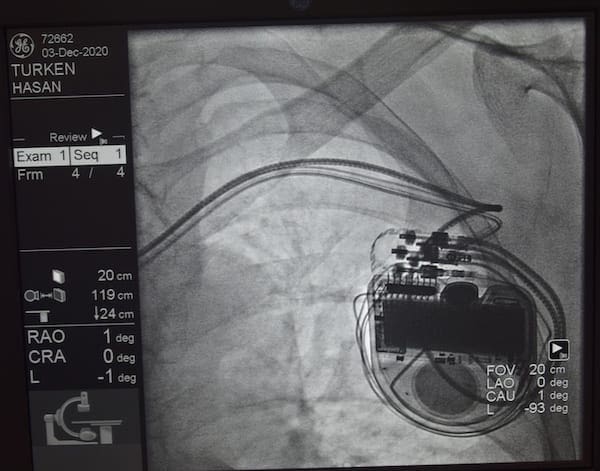

Düzce Üniversitesi Hastanesi’nde dal bloğu denilen ileti defekti olan kalp yetmezliği hastalarında, kalp yetmezliğine bağlı şikayetleri azaltarak, yaşam sürelerinin uzamasını sağlayan “Kardiyak Resenkronizasyon”...